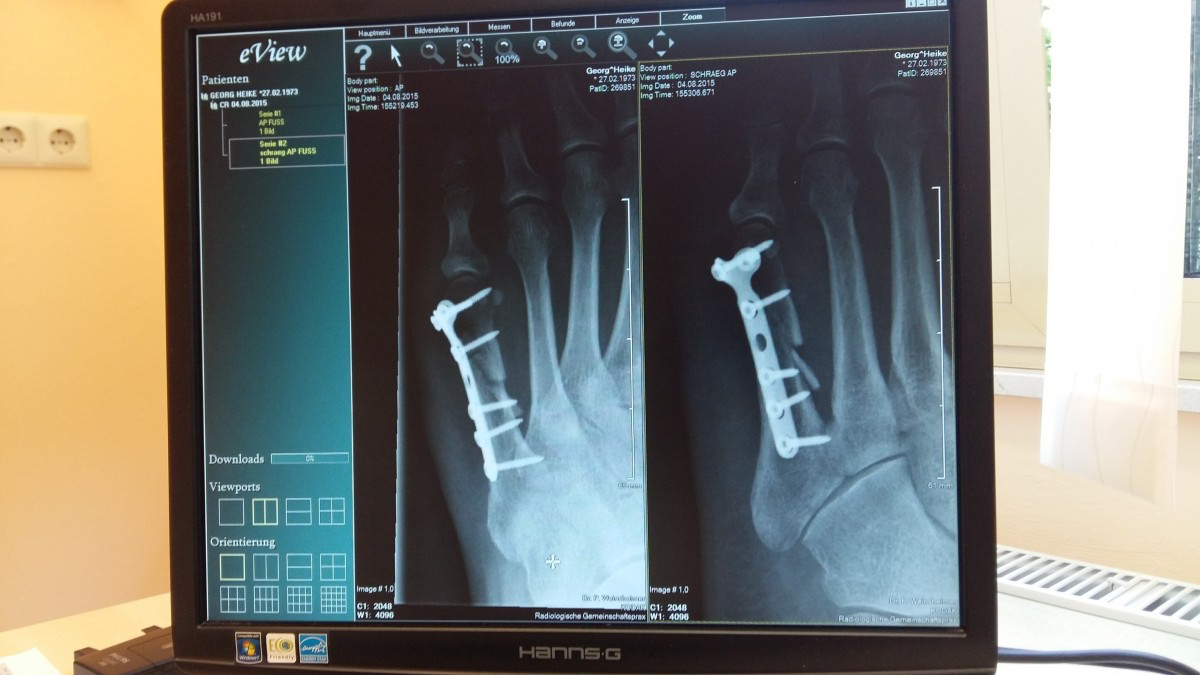

Röntgensäteily lääketieteessä

- Röntgensäteilyä käytetään lääketieteen kuvausmenetelmänä

- Perustuu eri aineiden kykyyn absorboida röntgensäteilyä (vuorovaikutus aineen elektronien kanssa)

- Säteily läpäisee paremmin kudosta kuin luuta (luu koostuu raskaammista alkuaineista kuin pehmytkudos)

Kuvat: Pxhere / CC0